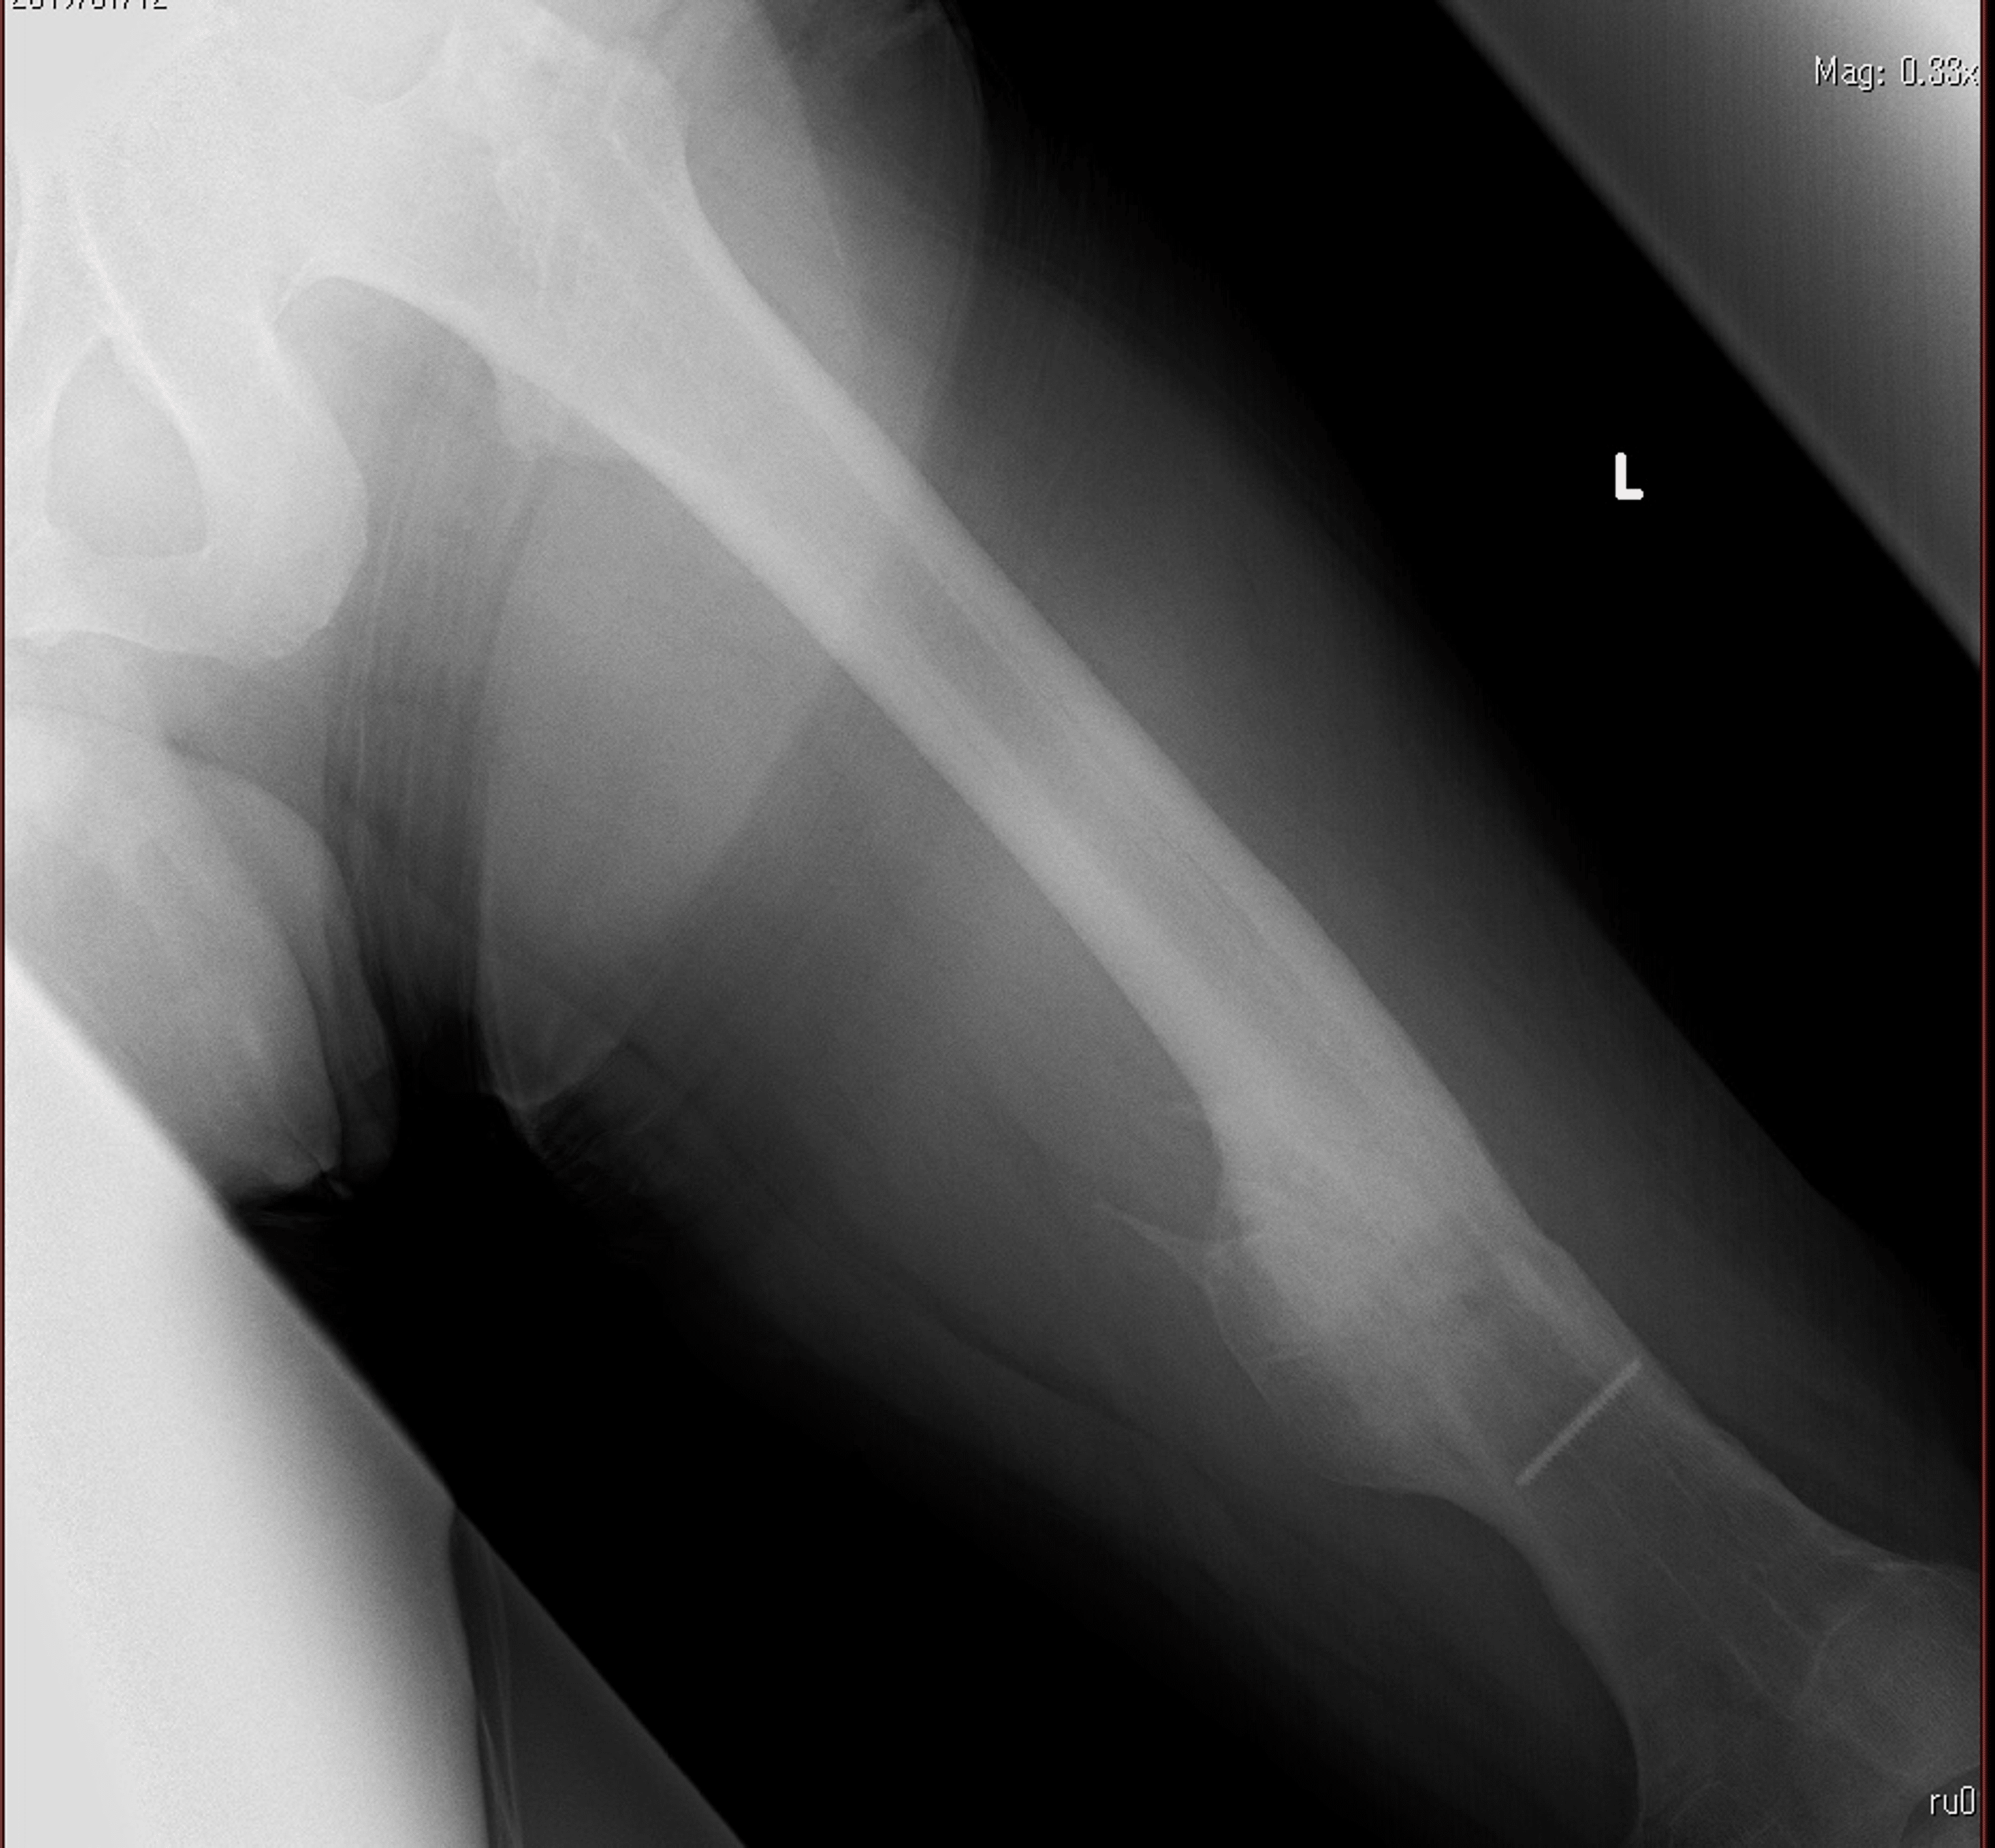

Gluteal Compartment Syndrome After Femoral Nail Extraction A Case Report Cureus Gluteal Compartment Syndrome Radiology We present three patients with gluteal compartment syndrome and review the clinical presentation, imaging, and laboratory. Compartment syndrome, an exceptionally rare condition, is a surgical emergency that can quickly escalate to limb. Gluteal compartment syndrome is a potential risk following total hip arthroplasty and is attributed frequently to body habitus and. Acute compartment syndrome is a painful condition caused by. Gluteal Compartment Syndrome Radiology.

Gluteal Compartment Syndrome After Femoral Nail Extraction A Case Report Cureus Gluteal Compartment Syndrome Radiology The gluteal region is a rare anatomic location for the. Gluteal compartment syndrome is an orthopaedic emergency that may be more prevalent and associated with a higher mortality rate (7% inpatient mortality) and. Gluteal compartment syndrome is a potential risk following total hip arthroplasty and is attributed frequently to body habitus and. Gluteal compartment syndrome is a rare, often unrecognized. Gluteal Compartment Syndrome Radiology.

Gluteal Compartment Syndrome After Femoral Nail Extraction A Case Report Cureus Gluteal Compartment Syndrome Radiology Gluteal compartment syndrome is a rare, often unrecognized syndrome that may. Gluteal compartment syndrome is a potential risk following total hip arthroplasty and is attributed frequently to body habitus and. Gluteal compartment syndrome is an orthopaedic emergency that may be more prevalent and associated with a higher mortality rate (7% inpatient mortality) and. Gluteal compartment syndrome is an orthopaedic emergency. Gluteal Compartment Syndrome Radiology.